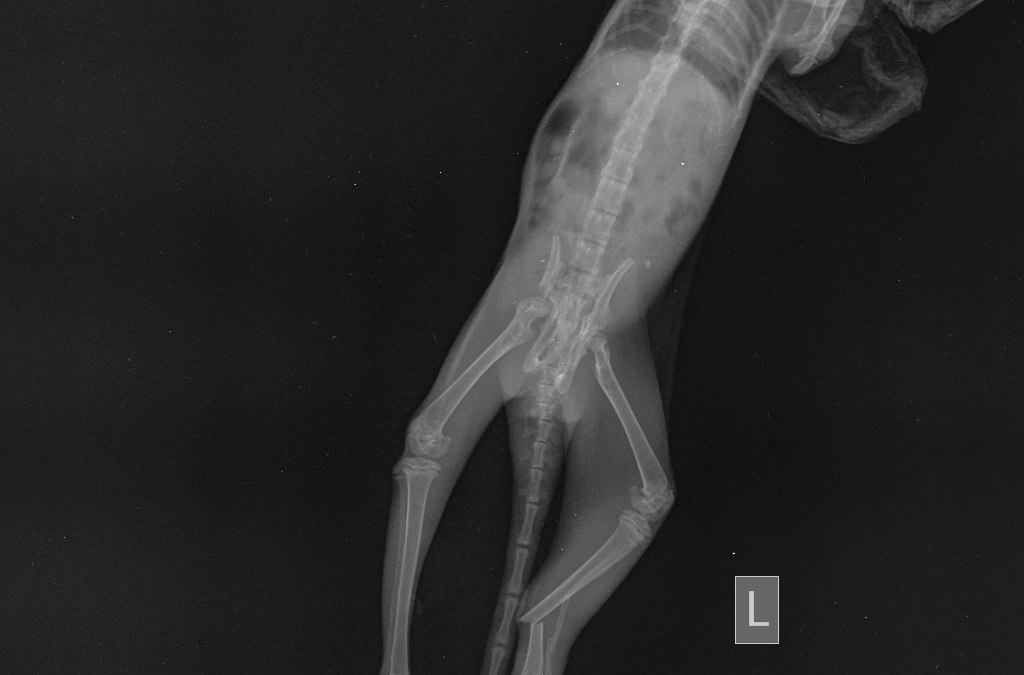

Остеосаркома может поражать как взрослых собаки так и молодых собак (встречается с 18 до 24 месяцев). Наиболее часто поражается нижняя треть лучевой кости, однако поражена может быть любая кость скелета (Рис.1, 2 ).

Рис. 1. Наиболее частые места поражения трубчатых костей остеосаркомой.

Рис. 2. Рентген грудной конечности собаки с остеогенной саркомой нижней трети лучевой кости (отмечено звездочкой).